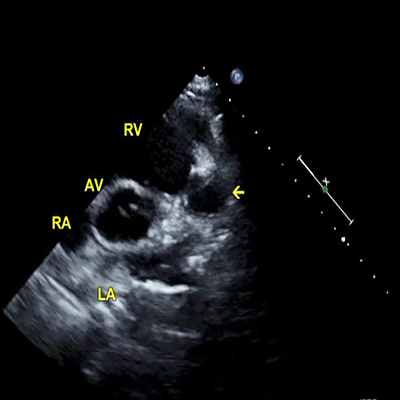

Rheumatic mitral stenosis

Rheumatic mitral stenosis